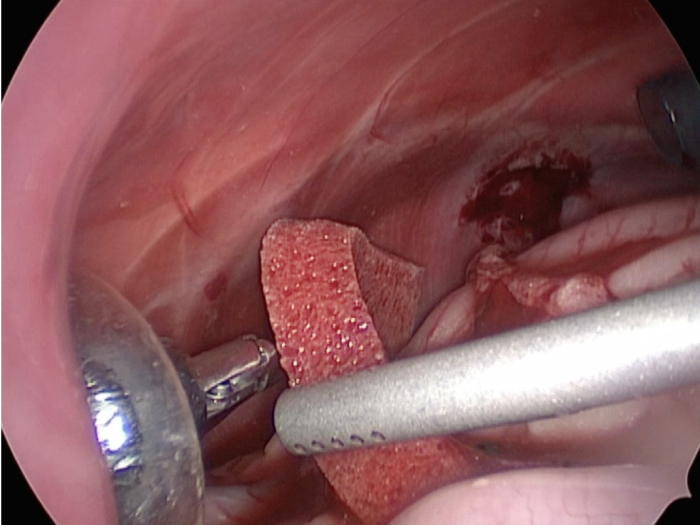

胆嚢の周囲の脂肪や膵臓、十二指腸が激しく癒着し剥離が困難な状態でした。 胆嚢は全く確認することができませんでした。

少しずつ癒着を剥がして胆嚢が確認できるようになってきました。

こんなに癒着していることはあまりないので過去に膵炎や胆嚢炎を起こし苦しい時期があったことが推測されました。

それにしてもなかなか胆嚢はでてきませんでした。

摘出した胆嚢はカチカチで中にはゼリー状の硬い物質が詰まっていました。

手術は丁寧に剥離していったため時間がかかってしまいました。

症状がなかったので、こんなに大変な状態になっているとは。